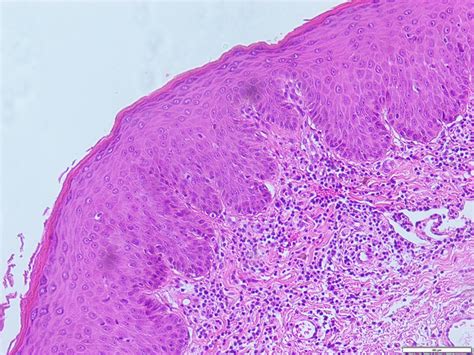

Histology Slide

H&E Stain (10x)

Biopsy reveals significant hyperkeratosis and acanthosis.

Cellular Changes: Loss of polarity and nuclear hyperchromatism confined to the lower third of the epithelium.

Critical Finding: Basement membrane is intact.

Answer: Mild Epithelial Dysplasia.

The intact basement membrane confirms it is NOT invasive Squamous Cell Carcinoma yet.